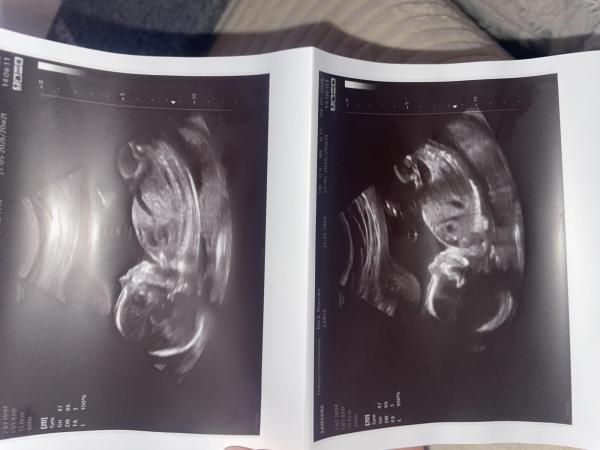

Hallo ihr Lieben, ich bin in der 21. ssw und hatte gerade mein zweittrimester screening, es wurde erst zu 75% ein Junge vermutet (beim ersten screening) und jetz hieß es doch ein Mädchen. Bin natürlich jetzt unsicher ob es auch wirklich so ist, was meint ihr ?  lg 🥰

Bild zu Geschlechtserkennung - Schwanger - wer noch? Rund um die Schwangerschaft

Guten Morgen Mareike,  ich meine, dass ihr da ein Hübsches Baby habt 🤭 Hoffe du nimmst es nicht falsch auf. Aber was soll dir hier jetzt jemand sagen? Hättest du jetzt ein Bild gepostet welches zwischen den Beinchen ist, dass man sagen kann: Männlein oder Weiblein, dann könnte ich die Frage ja verstehen.  Aber es war keiner beim Ultraschall dabei 🤷‍♀️ da wird dir keiner eine Aussage geben können, außer dein Arzt/Ärztin beim nächsten Termin. Drücke euch natürlich die Daumen, dass ihr sehr bald Gewissheit haben werdet.  Ganz liebe Grüße Cleo

Huu, schließe mich meiner Vorrednerin an, da gibt es für uns Laien wirklich nichts zu sehen, das Kind liegt dafür ja nicht günstig. Man braucht für Ultraschalldiagnostik außerdem viel Erfahrung und natürlich auch eine umfangreiche Ausbildung am Ultraschallgerät, so dass wir dir auf keinen Fall mehr sagen können als ein Arzt. Wichtig ist, dass es deinem Kind prima geht. Es ist ein wirklich hübsches Baby, an dem alles dran ist. Es wird sich schon noch sicher outen, wobei die Tendenz mit den 75 % Mädchen sich vermutlich bestätigen wird. Ich würde das jetzt erstmal glauben, wieso auch nicht. LG und noch eine schöne weitere Kugelzeit!

Also ich sehe auf den Bildern auch nichts  Was ich aber sagen kann ist das wahnsinnig oft das erste Screening falsch ist, deshalb sagen viele Ärzte so früh gar nichts